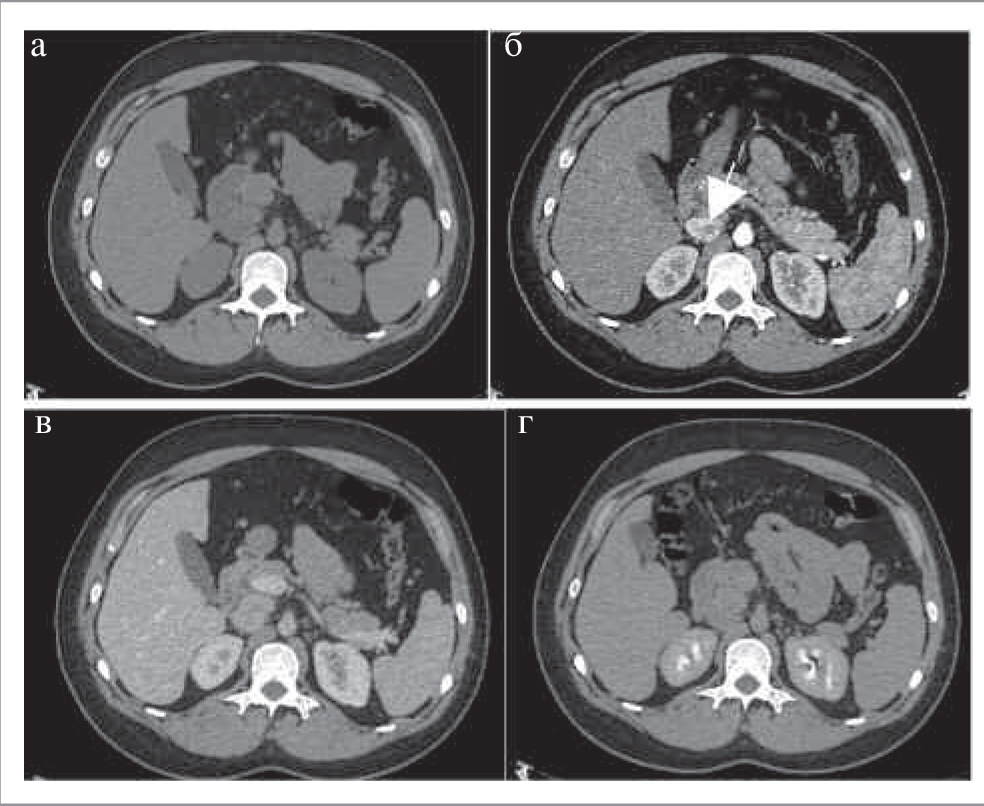

Как правило, АКР представляет собой крупное образование (от 2 до 40 см, в среднем 11–12 см) с неровными нечеткими контурами, повышенной плотности (более 10 ед. Н). При болюсном контрастном усилении образование умеренно неоднородно накапливает контрастный препарат со слабым его вымыванием в ОФ. Для данного образования характеры зоны некроза и кровоизлияний, а также кальцинаты, которые встречаются в 30% случаев [20]. При контрастировании возможно обнаружение тонкого капсулоподобного ободка контрастирования (рис. 7) [21]. Необходимо учитывать, что АКР также может быть выявлен в структуре таких доброкачественных образований, как аденомы (в структуре коллизионной опухоли); рис. 8.

Рис. 7. МСКТ, аксиальная проекция. Рак надпочечника. КТ-изображения в аксиальной проекции: а – НФ; б – АФ; в – ВФ; г – ОФ. В теле правого надпочечника определяется овальной формы образование (стрелка) с четкими ровными контурами, неоднородной структуры за счет наличия кальцинатов по периферии.

Рис. 8. МСКТ, аксиальная проекция. Коллизионная опухоль правого надпочечника (рак в структуре аденомы). КТ-изображения в аксиальной проекции: а – НФ; б – АФ; в – ВФ; г – ОФ. В правом надпочечнике определяется округлое образование (стрелка) пониженной плотности с четкими ровными контурами, неоднородной структуры за счет наличия центрально расположенного мягкотканного включения, интенсивно накапливающего контрастный препарат, со слабым его вымыванием в ВФ и ОФ.

Чаще поражается левый надпочечник, в то время как двустороннее поражение встречается менее чем в 10% случаев [20]. Для АКР характерны признаки злокачественности: инвазивный рост с вовлечением окружающих структур и органов или метастазы. Вовлечение почечной вены (9–19% наблюдений) чаще встречается при опухоли правого надпочечника и проявляется распространением опухоли в просвете данной вены, далее в нижней полой вене до правого предсердия [20]. Метастазы наиболее часто поражают легкие, печень, лимфатические узлы и кости.